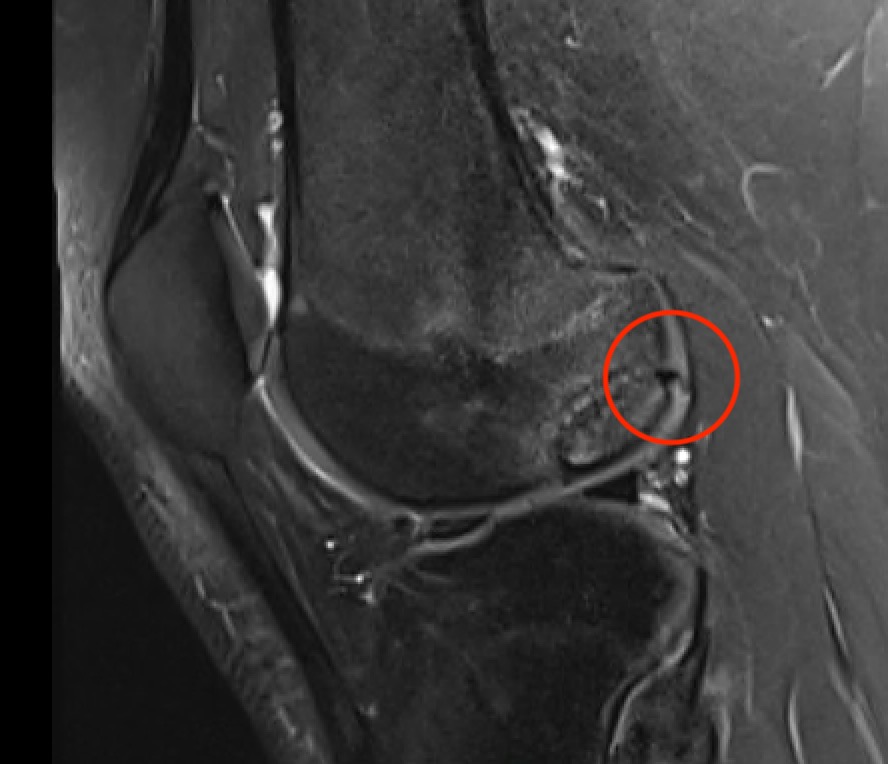

MRI Classification

Stage 1: Low signal changes, articular cartilage intact (stable)

Stage 2: Articular cartilage breached, low signal indicating fibrocartilage behind fragment (stable)

Stage 3: Articular cartilage breached, high signal indicating synovial fluid behind fragment (unstable)

Stage 4: Loose body (unstable)

Look for

- integrity of the articular cartilage

- fluid behind the lesion, suggesting instability

- displacement of the lesion

Stable

- no synovial fluid behind lesion

Unstable

- cartilage breach with synovial fluid behind lesion

Stage 1. Articular cartilage intact

Stage 2. Articular cartilage breach, but low signal intensity behind fragment

Stage 3. Articular cartilage breach and synovial fluid behind fragment (unstable)

Stage 4. Loose body

Minimally displaced loose body

Completely detached